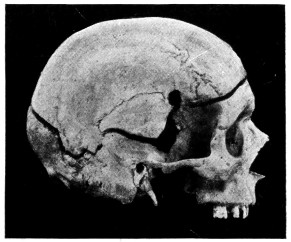

| 42. A comminuted fracture of the skull | 112 |

| 43 A and B. An explosive fracture of the vault of the skull | 113 |

| 44. A temperature chart illustrating the changes in temperature observed in head-injuries | 117 |